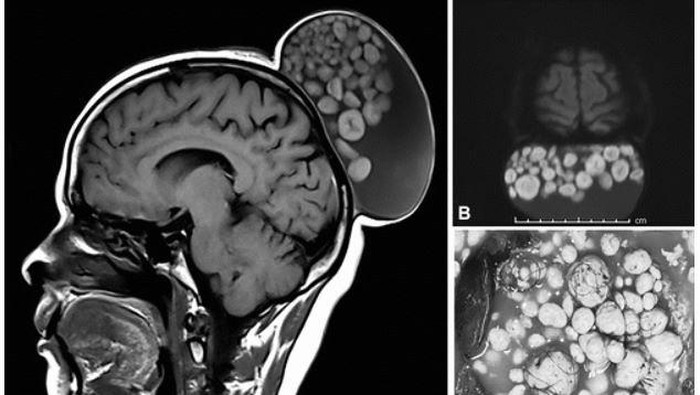

Saat sampai di RS, wanita itu langsung menjalani pemindaian MRI yang menunjukkan massa berukuran panjang 15 cm, lebar 10 cm, dan tinggi 12 cm di kepalanya.

Dokter mengatakan pertumbuhan jaringan abnormal yang ditemukan bersembunyi di dalam kista memiliki 'beragam variasi ukuran'.

Berdasarkan hasil pemeriksaan mikroskopis, kista yang tumbuh di kepala wanita itu adalah kista dermoid atau dikenal secara medis sebagai teratoma kistik matur. Menurut National Health Service UK (NHS), kista dermoid yang tidak bersifat kanker biasanya berkembang dari sel embrionik yang mengandung rambut, cairan, gigi, atau, kelenjar kulit.